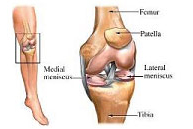

La articulación de la rodilla está formada por las partes inferior del fémur, superior de la tibia y posterior de la rótula actuando como una gran bisagra. Es la articulación más lesionada en el deportista y su tratamiento exige un gran conocimiento de la anatomía así como de la cirugía traumatológica, protésica y artroscópica.

Lesiones ligamentosas de rodilla